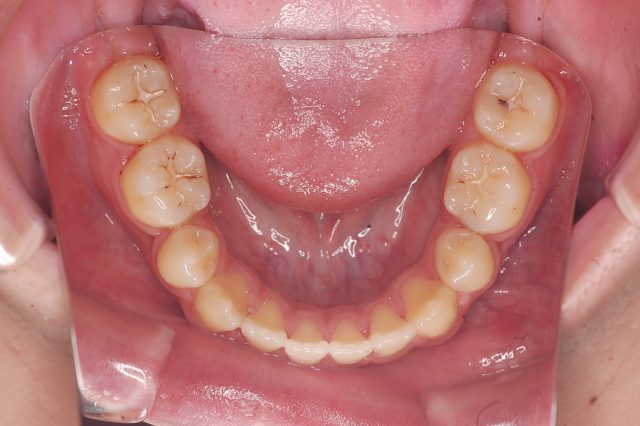

Before

After

主訴

前歯で噛めない

治療期間・回数

2年6ヶ月・30回

治療方法

マルチブラケットにて上下左右4本抜歯

費用

850000+税

デメリット・注意点

歯根吸収 歯肉退縮